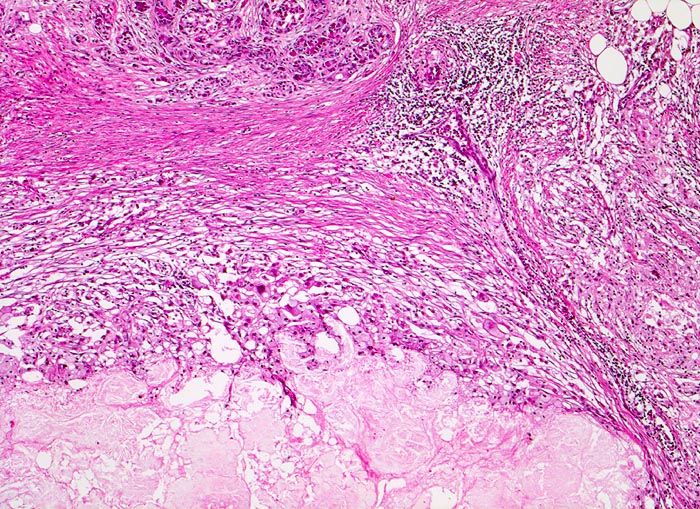

Breite Bänder von sklerosiertem zellarmem Bindegewebe verlaufen zwischen den Läppchen.

Atrophie des exokrinen Pankreas.

Erhaltene Inseln und Gangstrukturen.

Spärliches chronisches Entzündungsinfiltrat.

Rechts oben ist eine partiell vom Rand her durch Granulationsgewebe organisierte lytische Fettgewebsnekrose erkennbar. Diese ist Folge eines akuten pankreatitischen Schubs.